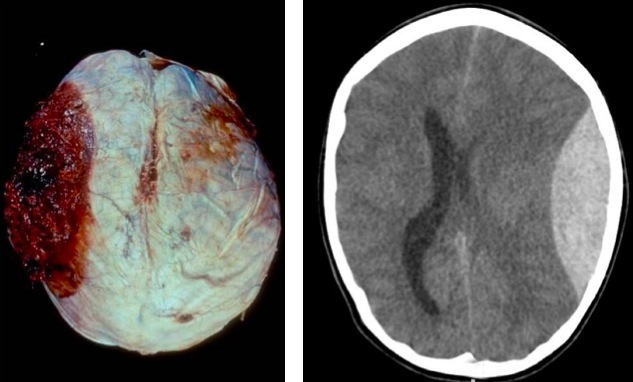

Epidural hemorrhage

Subdural hemorrhage